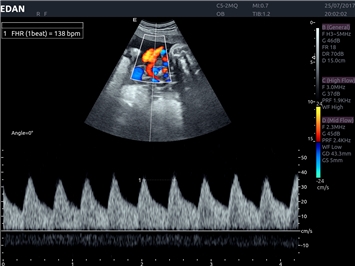

• Автоматизированные измерения в акушерстве

• Акушерства и гинекологии

Импульсно-волновой допплер:

Да